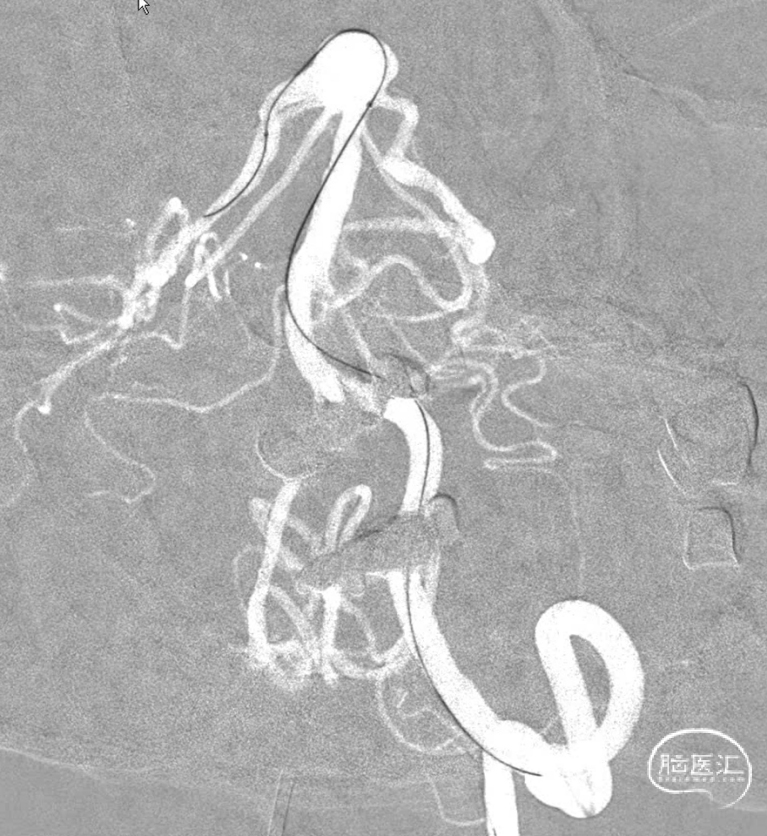

先填一个适当大小的圈,刚开始微导管头位置感觉差一些,借着弹簧圈比较软的优势,适当跟了一点微导管,感觉这个位置应该可以了,首先因为是大动脉瘤,通过简单的填塞很难把动脉瘤栓塞致密,因此一般选择分区填塞,因此计划是先把8,9点位置填的差不多后再回撤微导管,在回撤轨迹将弹簧圈依次填塞使其致密,但是凡事都是:身后有余忘缩手,眼前无路想回头。所以一切计划都存在变数。

第一个圈盘的还可以,直接支架辅助,一切都很顺利。微导管头的位置按原计划可行。

第一个圈填完,成型不错,弹簧圈微导管由于圈的张力作用,稍好低了一下头(红色标记),不过还好。

连续填了两枚圈,微导管头没变,但是开始左右摆圈。不好,根据以往经验,瘤顶偏右侧的空间要丢掉机会,如果再填一个圈,即将把动脉瘤颈部偏右侧大脑后动脉部分填致密,这样的话残留在瘤顶部的空白处可能填不上,因此直接采取下一方案。于是趁着瘤颈还有空间,将右侧支架导管撤下,将头塑型为指头或单弯,穿支架网孔到位。

这是微导管到位就放心了,但是一定注意,穿网孔微导管可能有阶梯效应,使其弹射,因此一定要控制好张力,减少戳破动脉瘤的风险。

管他如何,先填个圈把这一部分添上。接下来就是考虑把动脉瘤偏左侧进行正常填塞。

动脉瘤右侧是没事了,但是左侧好像失策了,可以看到左侧部分有一部分圈,但是还是不太致密,但是由于弹簧圈微导管由于在填弹簧圈时,不断减张力,因此已经离开了原来计划的位置。千算万算,好像还是忽略了这一点。

造影显示,左侧大脑后动脉起始似乎还是受到圈的小小影响,最终决定还是把支架放上。